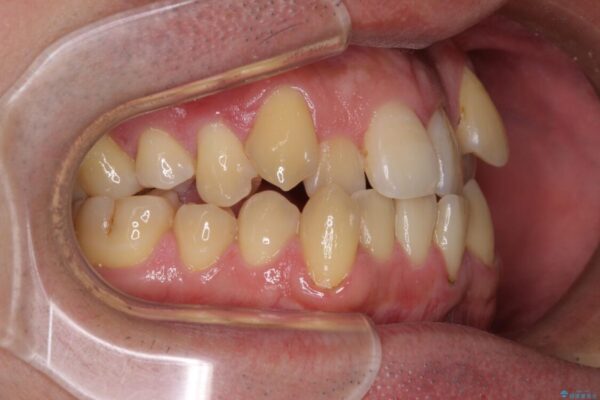

八重歯と前歯のクロスバイトを改善したいとのことで来院された患者様です。

デコボコの程度は強かったのですが、口元の突出感はなかったため、非抜歯矯正としました。

治療前

• 八重歯とクロスバイト 目立たないワイヤー装置で矯正治療 治療前画像